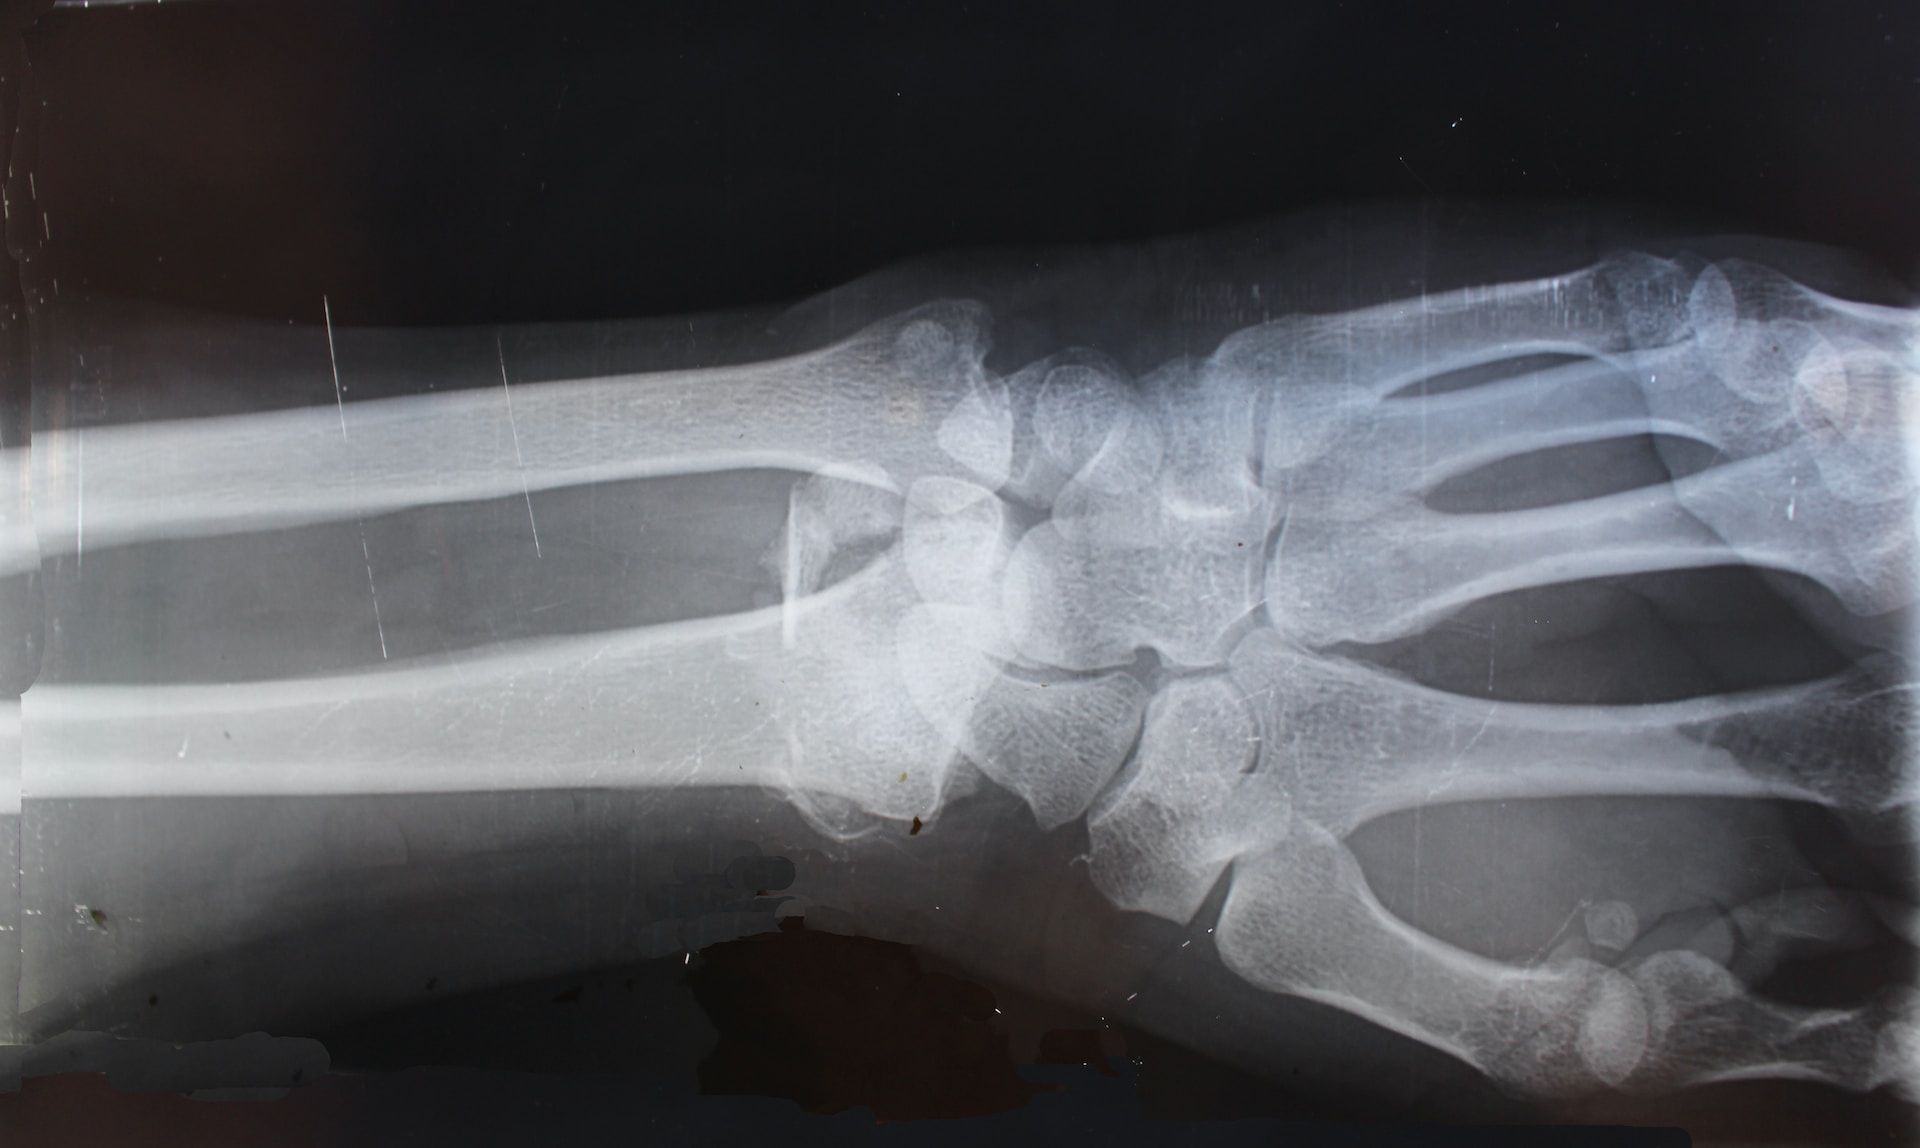

如果有以上症状,建议可以到医院做X光做进一步检查,如果有发现退化的症状就要积极治疗,防止持续恶化。